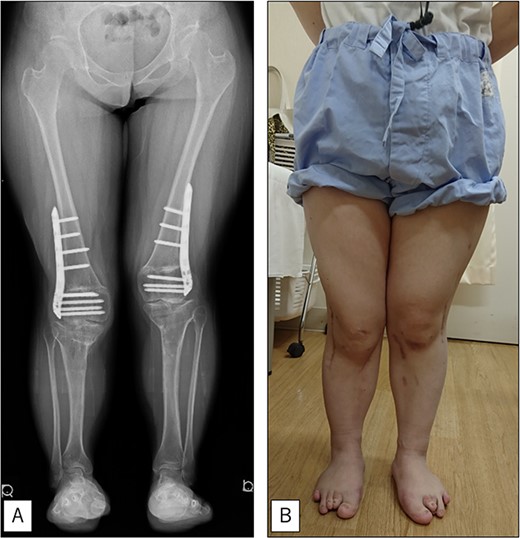

A 23-year-old woman presented with bilateral knee pain and gait abnormalities owing to marked lower extremity deformity. She was diagnosed with EVC as a child but had never been followed up by orthopedics because she was not in pain. On physical examination, marked valgus instability was observed in both knees, and the motion of both knees ranged from 10° to 135°. Radiographic examinations of both knees, including computed tomography, showed valgus deformity, lateral and anterior depression of the proximal lateral tibial plateau, and external rotation deformity of the lower leg. Patellar dislocation was observed in the right knee (Fig. 1). The radiological angles are presented in Table 1. The right knee underwent surgery first, followed by the left 10 months later. Lateral and medial skin incisions were made. Extensive lateral retinacular release, fractional lengthening of the distal lateral hamstring, and Z-lengthening of the iliotibial band were then performed. At this stage, peroneal nerve strain was identified, and decompression of the peroneal nerve was performed. Osteotomy was subsequently performed on the tibia. Closed-wedge varus and derotational osteotomy of the proximal tibia and open-wedge varus osteotomy of the distal femoral varus were performed. In addition, vastus medialis advancement was performed on the right knee, and patellar realignment was achieved in extension (Fig. 2). However, the knee showed a subluxation tendency owing to flexion of >30°; therefore, the postoperative rehabilitation plan progressed more slowly than that of the left knee. Range of motion training began on the left knee immediately after surgery without any restrictions, but on the right knee only after 3 weeks of postoperative immobilization in the extended position. However, ambulation exercise was performed on both knees with no loading for 3 weeks, then partial loading was initiated, and full loading was permitted at 8 weeks postoperatively. Early postoperative standing radiography showed residual mild valgus deformity of the lower limbs (Fig. 2, Table 2). In addition, the right knee showed patellar re-dislocation 2 months postoperatively, and the patellar deformity gradually progressed owing to the femoral implant; therefore, the patient underwent implant removal, tibial tubercle transfer, and medial patellofemoral ligament reconstruction 1.5 years after the initial surgery (Fig. 3). Six months later, she fell while walking and developed a fracture at the osteotomy of the right femur; open reduction and internal fixation were performed (Fig. 4). The remaining years passed uneventfully, and 10 years after the initial surgery, the patient still had mild valgus deformity of the lower limbs, but had no recurrence other than that experienced immediately after surgery, no complaints of knee pain, and a stable gait (Fig. 5, Table 2).

At the final follow-up 10 years after the initial surgery. (A) Standing anteroposterior view. Although mild valgus deformity of the lower limbs remained, no recurrence occurred except for that experienced immediately after surgery. (B) Photograph of the entire lower legs.